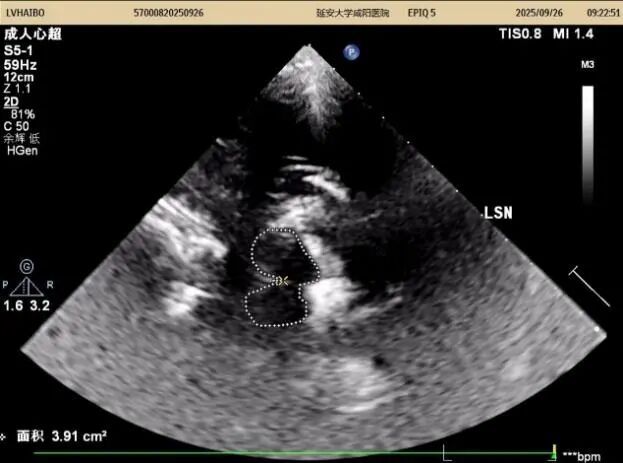

26日上午及下午14:00至15:50,以實(shí)際病例為媒介全流程質(zhì)控,從設(shè)備調(diào)試、探頭的選擇與放置、中腦(黑質(zhì)、紅核、導(dǎo)水管)、丘腦、第三腦室、豆?fàn)詈藚^(qū)域等的識(shí)別,到圖像優(yōu)化與測(cè)量規(guī)范,逐步演示標(biāo)準(zhǔn)操作流程,重點(diǎn)解析黑質(zhì)高回聲的識(shí)別與鑒別診斷。期間,結(jié)合患者病史,耐心答疑、細(xì)致指導(dǎo),引導(dǎo)醫(yī)師多維度理解技術(shù)要點(diǎn),提升實(shí)戰(zhàn)能力。同時(shí)對(duì)我科前期工作給予高度評(píng)價(jià)。

在專(zhuān)題授課環(huán)節(jié),張教授以《帕金森病的TCS與神經(jīng)調(diào)控專(zhuān)家共識(shí)-解讀與臨床應(yīng)用》為題,從帕金森病的發(fā)病率及早期診斷難點(diǎn)切入,以問(wèn)題為導(dǎo)向,結(jié)合國(guó)內(nèi)外研究,系統(tǒng)講解了中腦黑質(zhì)超聲的設(shè)備要求、檢查體位、標(biāo)準(zhǔn)切面及關(guān)鍵核團(tuán)評(píng)估要點(diǎn),并通過(guò)典型圖像與病例,深入闡釋影像特征與臨床表現(xiàn)的關(guān)聯(lián)。針對(duì)實(shí)際工作中常見(jiàn)問(wèn)題進(jìn)行了重點(diǎn)強(qiáng)調(diào),現(xiàn)場(chǎng)學(xué)術(shù)氣氛濃厚。王英莉主任總結(jié)指出,開(kāi)展TCS需做到“準(zhǔn)、慢、細(xì)”—診斷精準(zhǔn)、隨訪耐心、觀察細(xì)致,并強(qiáng)調(diào)各亞專(zhuān)業(yè)組應(yīng)加強(qiáng)與臨床科室的縱深交流,融入科研思維。